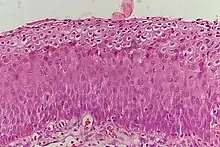

CIN is classified in grades:[14]

| Histology Grade | Corresponding Cytology | Description | Image |

|---|---|---|---|

| CIN 1 (Grade I) | Low-grade squamous intraepithelial lesion (LSIL) |

|

| CIN 2/3 | High-grade squamous intraepithelial lesion (HSIL) |

| CIN 2 (Grade II) |

| CIN 3 (Grade III) |